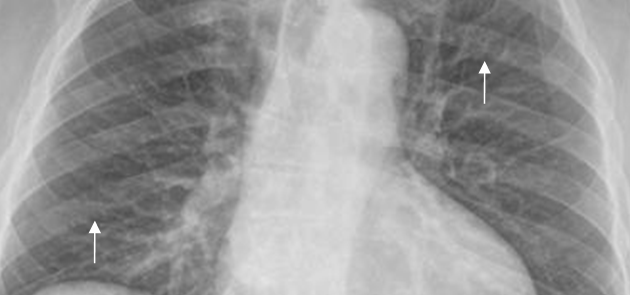

El borde costal superior es liso y bien definido en toda su longitud. Hay pérdida en la nitidez del contorno inferior, por la interposición del paquete vasculonervioso. Este hallazgo es simétrico, no debe ser confundido con patología y es mas encontrado en las costillas del tercio medio. (3). (Fig 8).

Fig 8. Costillas normales.

Rx PA. Pérdida de la nitidez en el borde inferior de las costillas, por la interposición del paquete vasculonervioso.